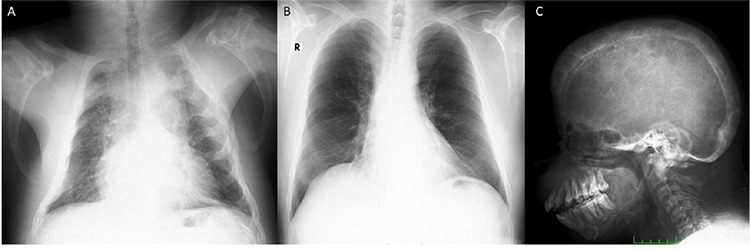

Sagliker syndrome (SS) is a rare, exaggerated form of chronic kidney disease (CKD)-mineral and bone disorder resulting from untreated secondary hyperparathyroidism due to CKD. Herein, we describe a 34-year-old male patient whose Tc-99m-methylene diphosphonate bone scintigraphy and Tc-99m-sestamibi parathyroid scintigraphy revealed hints of SS and exhibited its defining characteristics.